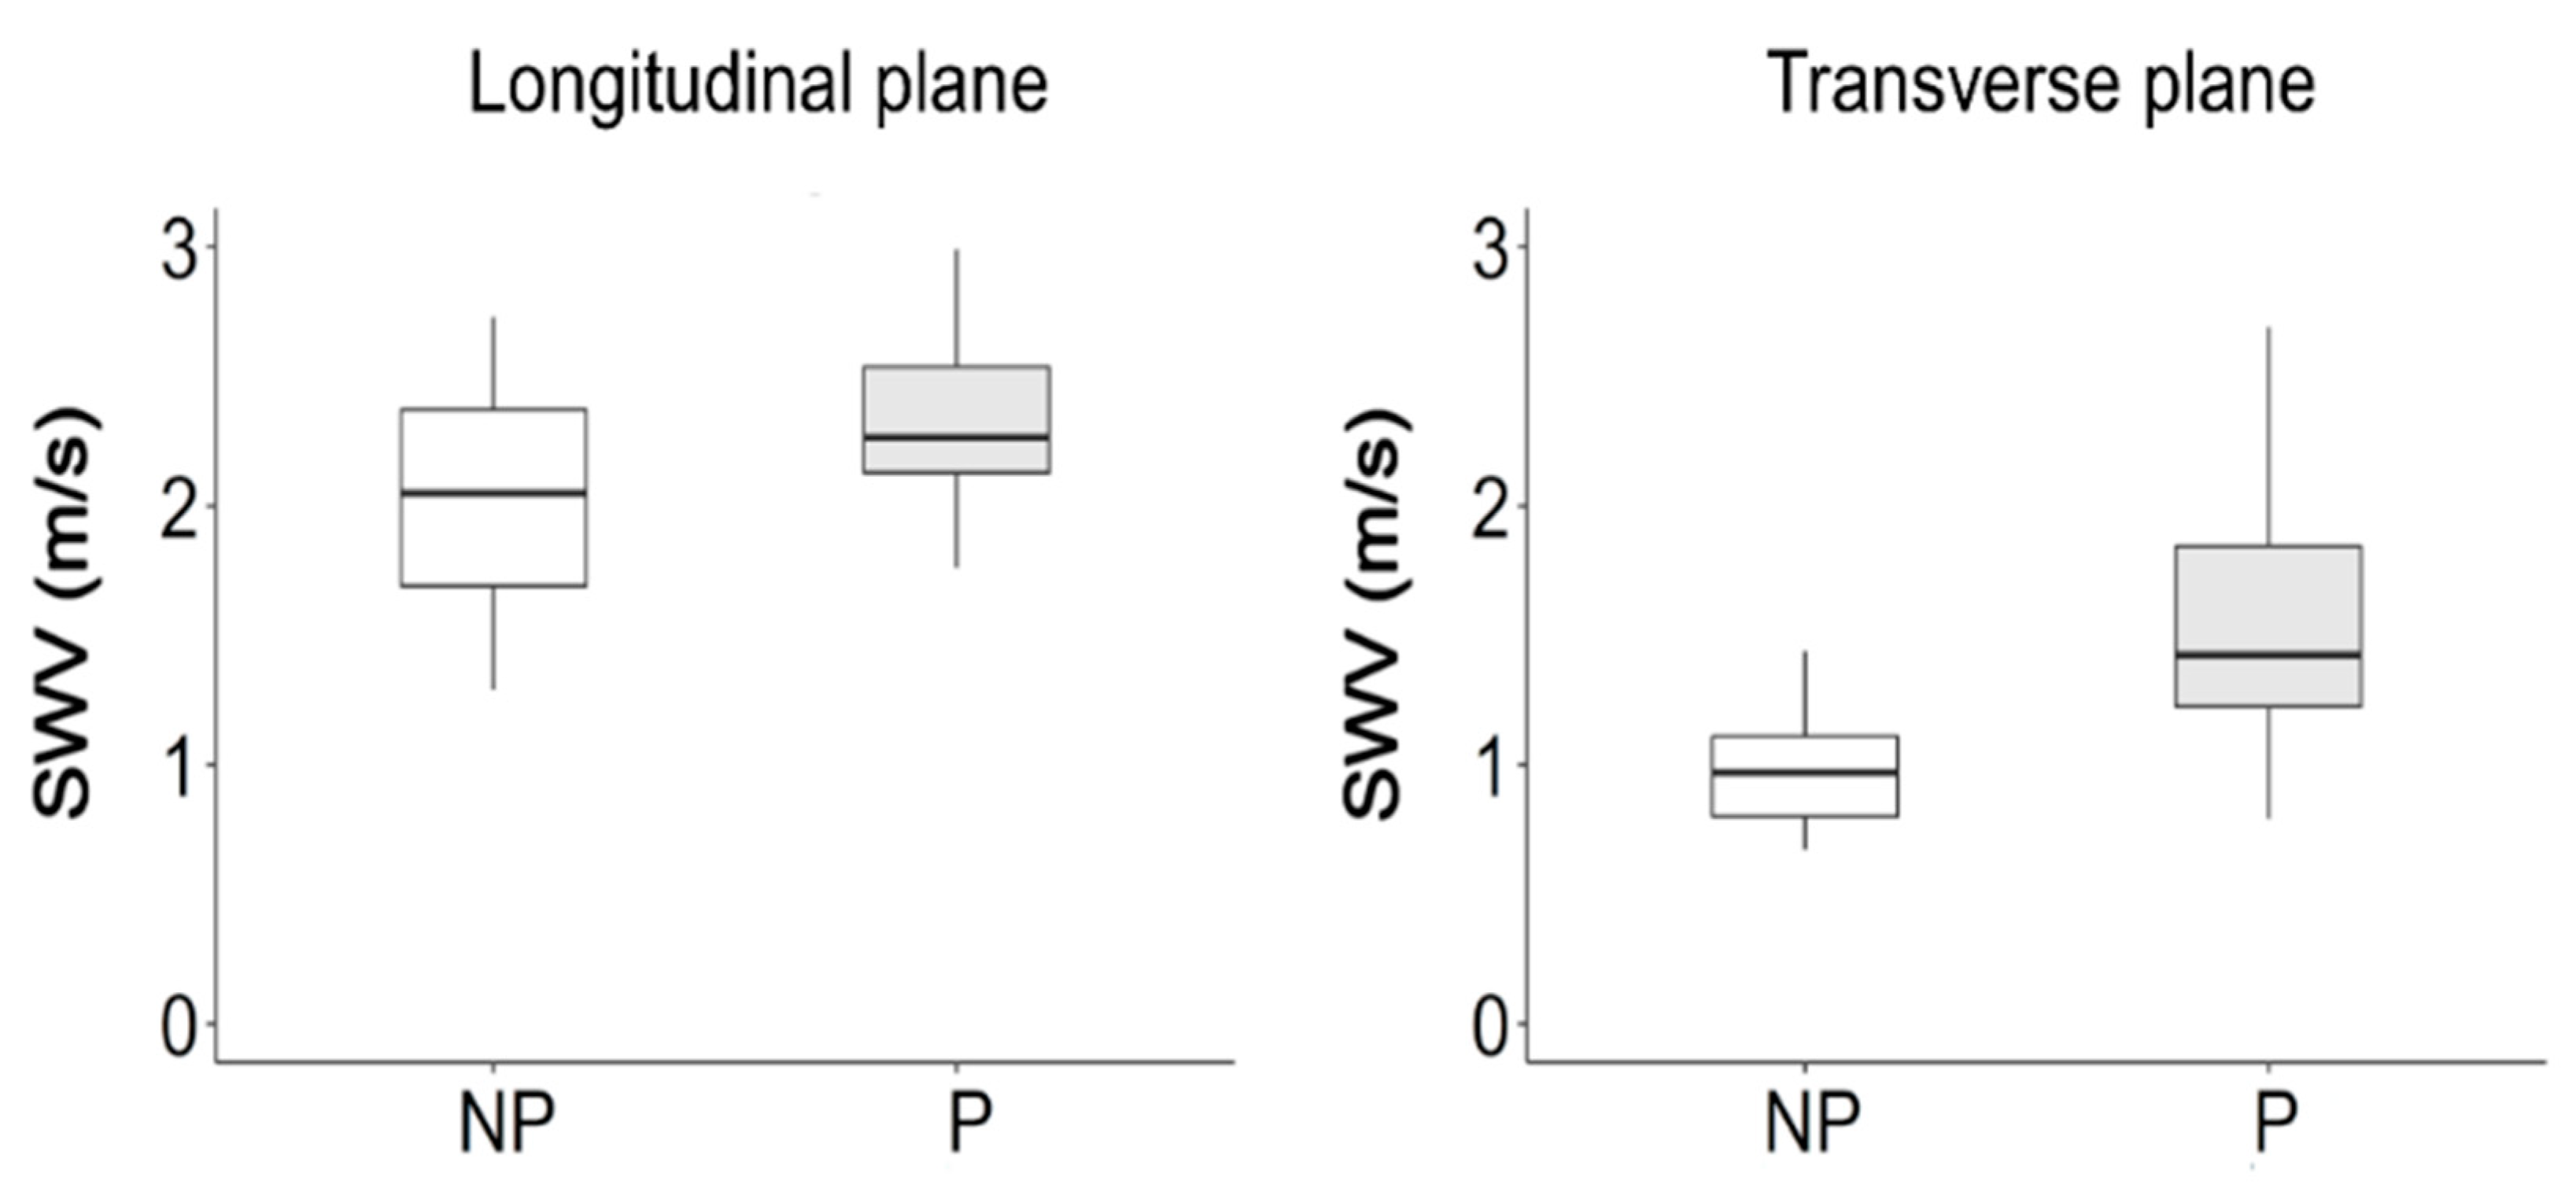

3. Results

4.2. Fiber Orientation and Shear Wave Velocity